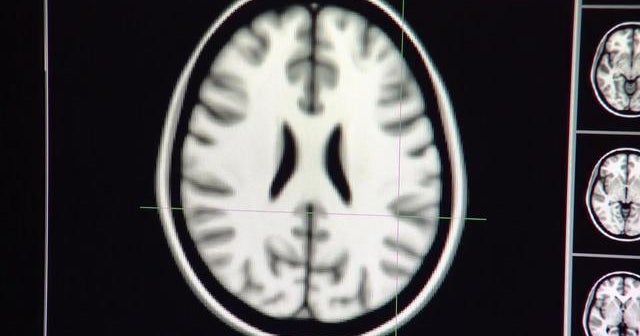

Heavy teen marijuana use may cause memory problems

New research shows the effects of heavy marijuana use among teenagers. And, UCLA researchers are closer to developing a blood test to diagnose Alzheimer's. Eboni Williams has a look at some of the day’s top health stories.